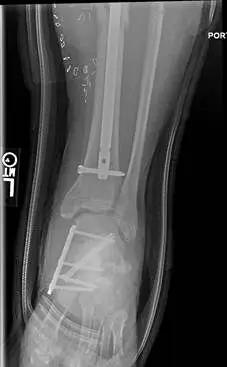

These are pics of an open midfoot fracture and dislocation after a motor vehicle accident.

These are pics of the external fixator on to hold temporary reduction prior to internal fixation

These are pics of the plate and screws stabilizing the fractures after ex fix was removed. An IM rod was also placed for a tibia fracture.